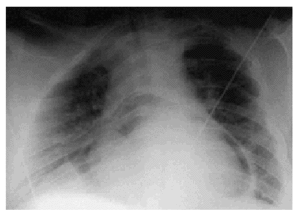

Varón de 32 años de edad, obeso, con síndrome de Down y antecedentes personales de ductus arterioso intervenido en la infancia y derrame pericárdico crónico grave. En la última ecocardiografía de control efectuada, se apreciaba un derrame pericárdico circunferencial grave con cambios inspiratorios en los flujos mitral y tricúspide y una dilatación de la vena cava inferior. Ante estos signos de compromiso hemodinámico, se decidió realizar pericardiocentesis percutánea. Se extrajeron 1.100 ml de un líquido ambarino y translúcido, y se dejó colocado un catéter de drenaje. En la radiografía de tórax de control realizada unas horas más tarde (fig. 1) podemos apreciar un importante neumopericardio. Al día siguiente, se retiró el citado drenaje por ser muy escaso el débito a través de él.

Figura 1.